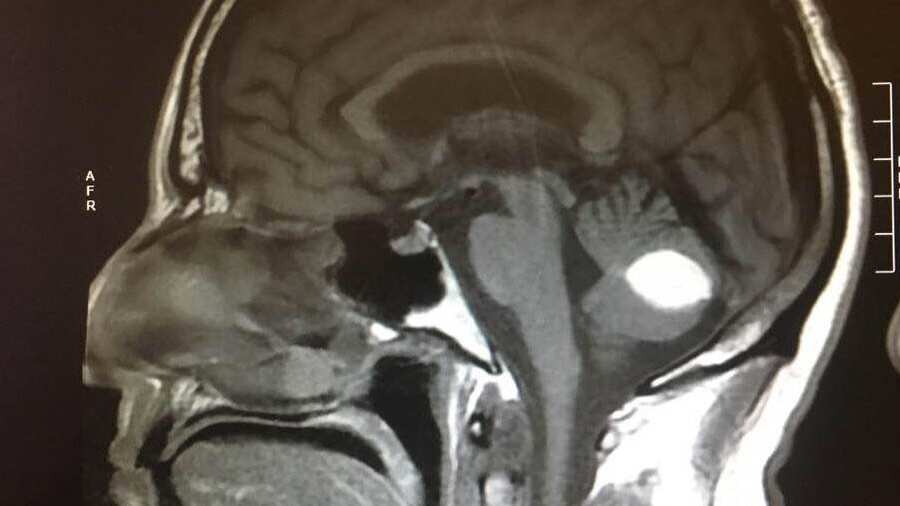

«Si no crees en Dios y crees que no hace milagros, explica esto. El tumor desapareció y los médicos no puede explicarlo, están de acuerdo en que se trata de un milagro», escribió en Facebook mostrando una fotografía de la tomografía en la cabeza que le hicieron en el hospital.

«Esto (la tomografía) fue en julio del 2018, en la parte inferior derecha se puede ver el tumor en el lugar del círculo blanco, ahora ha desaparecido», explicó el paciente.